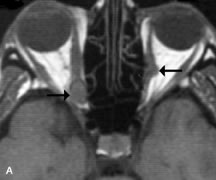

Extraocular muscle enlargement in patients with thyroid-associated orbitopathy is demonstrated equally well with CT and MRI studies. However, the superior tissue contrast on MR images reveals better details of the relationships of the optic nerve to the thickened muscles at the orbital apex (Fig. 16).50 In addition, MRI may be able to differentiate between muscles that are enlarged as a result of edema and active inflammation and those enlarged because of fibrosis by their T2 relaxation times.21 Quantitative MRI was not found to be accurate in predicting the success of low-dose orbital irradiation.51 However, a muscular index relating the diameters of the rectus muscles to the bony orbital dimensions was useful in predicting optic nerve compression.52

Fig. 16. A-C, T1-weighted MR scans obtained with a high-resolution surface coil demonstrate fusiform enlargement of the extraocular muscles. The medial, lateral, and inferior rectus muscles are especially involved. Note the relative sparing of the tendinous insertions, a finding characteristic of this disease process, as well as fatty infiltration of the lateral and inferior rectus muscles. There is marked proptosis, best visualized on the sagittal image (A), and mild crowding of the optic nerve at the orbital apex.